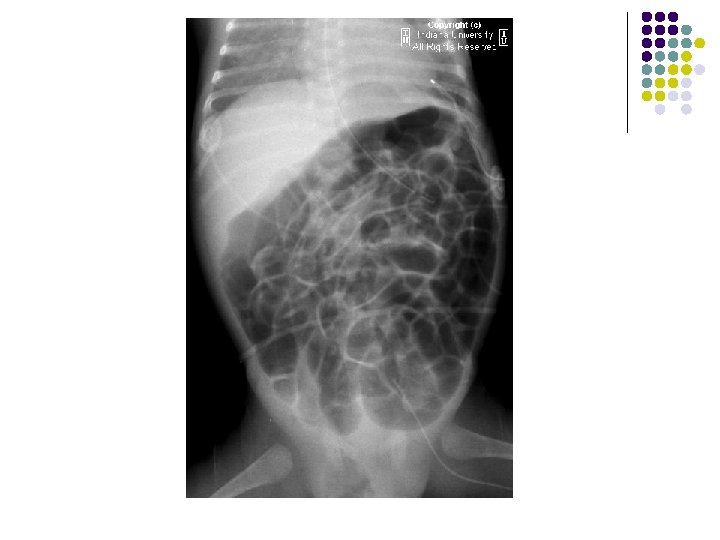

IMAGING FEATURES l Plain abdominal film: A well-defined right lower quadrant mass. l Contrast enema: Smooth indentation of the medial aspect of the cecum & non-opacification of the appendix. l Ultrasound: Completely anechoic or hypoechoic with variable internal echogenicity and Whorled appearance is characteristics due to internal contents May have posterior acoustic enhancement. with variable wall thickness and calcification.

FINDINGS l Supine AP radiograph of the abdomen reveals a normal abundant bowel gas pattern with no evidence of obstruction. l However, gas is seen within a small bowel loop in the right inguinal region. l Delayed supine AP images of the abdomen from a small bowel series demonstrates contrast within a small bowel loop within the right hemiscrotum.

RADIOLOGICAL FEATURES: ON PLAIN RADIOGRAPH: l A loop of air filled bowel will be seen outside the expected location of the abdomen/pelvis. l Occasionally, bowel will be visualized within the scrotum. l Further imaging is usually not needed. SMALL BOWEL FOLLOW THROUGH: l Contrast within a small bowel loop in the right inguinal canal. l Ultrasound is the imaging modality of choice in adults. A loop of bowel demonstrating peristalsis within the inguinal canal is diagnostic. The exam is performed at rest and with the valsalva maneuver in order to diagnose easily reducible hernias.